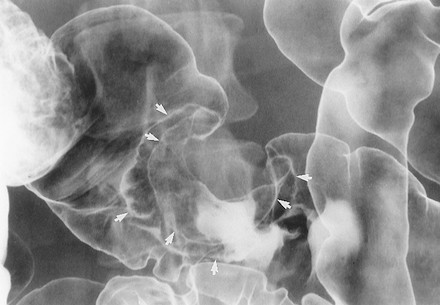

3.1.3. U tuyến lông nhung (villous adenoma)

Các u tuyến có sự thay đổi lông nhung mao mức độ cao gọi là u tuyến lông nhung. Chúng là một dạng đặc biệt vì có nguy cơ thoái biến ác tính cao hơn các u tuyến ống hoặc u tuyến ống-lông nhung. Các u tuyến lông nhung có thể nhận ra trên các ảnh cản quang kép dưới hình các tổn thương polyp có bề mặt lưới hoặc nốt do baryt kẹt giữa các lông của khối u (Hình 7) [4].

Các khối u tuyến lông nhung có thể là các tổn thương chia thùy, phẳng, còn gọi là các tổn thương hình “tấm thảm”, chúng được mô tả là các thay đổi tinh vi ở bề mặt đại tràng, lồi rất ít hoặc không lồi vào lòng đại tràng. Kích thước trung bình của u 4 x 6 cm, thường mọc ở trực tràng, manh tràng, và đại tràng lên. Trên phim cản quang kép nhìn thẳng, các nốt to, nhỏ tụ với nhau thành mảng, phân cách nhau bởi các lưới mảnh đọng baryt (Hình 8) [5]. Khi nhìn nghiêng, tổn thương có bờ không đều, trái với bờ nhẵn của niêm mạc bình thường bao quanh.

Hình 7. Hình cản quang kép nằm ngửa cho thấy khối u tuyến lông nhung ở trực tràng. Tổn thương là khối dạng polyp (các mũi tên) với bề mặt nốt và lưới.

Hình 8. Hình cản quang kép chếch sau phải bộc lộ một tổn thương hình thảm. Chú ý bề mặt hình lưới-nốt của tổn thương (mũi tên) ở manh tràng do baryt lấp đầy các kẽ hở của khối u tuyến lông nhung.